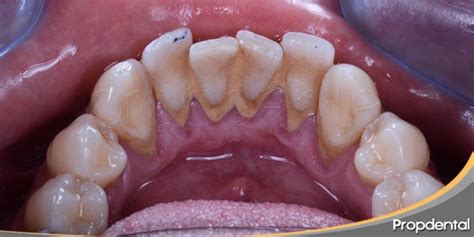

El sarro, también conocido como cálculo dental, es una acumulación endurecida de placa bacteriana que se forma en los dientes y puede dañar el esmalte dental y provocar caries. El sarro, a veces denominado cálculo o tártaro dental, es la placa que se ha endurecido en los dientes debido al depósito de minerales.

A diferencia de la placa que es una película incolora, el sarro presenta minerales siendo fácilmente visible si se localiza por encima de la línea de las encías. El indicador de sarro más común es observar un color marrón o amarillento en los dientes o encías. Al ser más poroso, absorbe fácilmente las manchas.

El sarro no sólo amenaza la salud de dientes y encías, también es un problema estético. También puede formarse por encima y por debajo de la línea de las encías y puede irritar el tejido gingival. Cuando no se erradica a tiempo, el sarro puede acumularse sobre y/o entre los dientes.